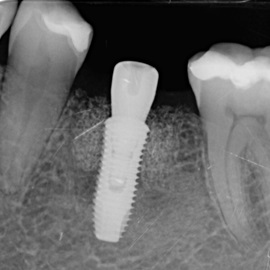

Odbudowa lewego dolnego trzonowca.

Odbudowa prawego dolnego trzonowca.